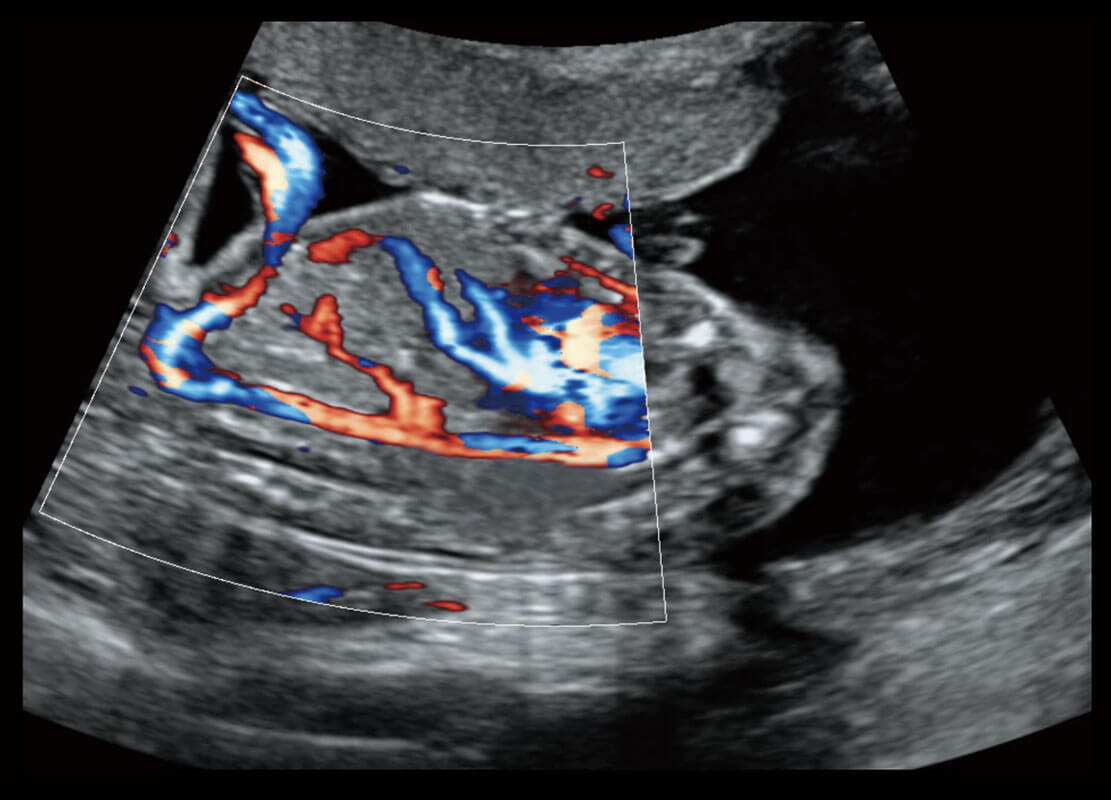

乳腺超声 / 新生儿

P60搭载宽频带线阵探头、宽景成像、弹性成像技术,为您提供乳腺应用方案。P60支持高频相控阵探头、线阵探头、腹部高频探头、腹部微凸探头等,丰富的探头群搭载敏感的彩色血流成像,适用于新生儿多种脏器检测要求,满足新生儿筛查需求。

• 新生儿肝血管癌